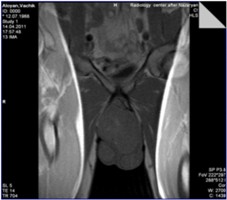

Զննման տվյալներով` արտաքին սեռական օրգանները զարգացած են արական տիպի, շեքի` առավելապես միզասեռական շրջանում, առկա էր մոտ 12,0 x 7,0սմ չափերի, անհարթ մակերեսով, պինդ-էլաստիկ կոնսիստենցիայի, համեմատաբար հստակ եզրագծերով, սահմանափակ շարժունակությամբ ուռուցքային գոյացություն, որի պրոյեկցիայով մաշկնանփոփոխ էր, շարժունակությունը` պահպանված: Ամորձիների չափերը և կոնսիստենցիան պահպանված են` հրված վեր: Աճուկային շրջանների շոշափումը մեծացած ավշահանգույցներ չի հայտնաբերել (նկ.1):

| Նկար 1 | |